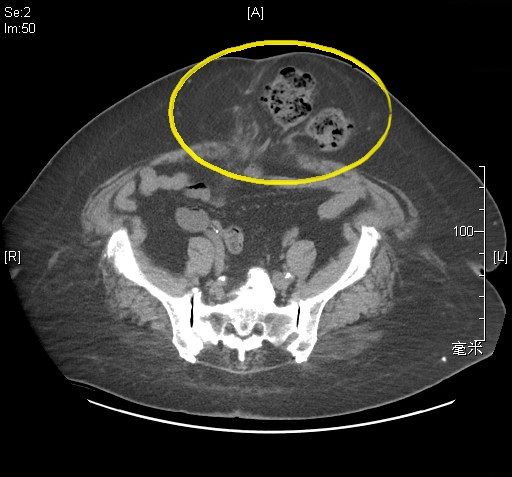

《圖說》黃崧峰醫師說明,電腦斷層影像顯示腹部手術傷口處出現疝氣,導致腸道突出(黃圈處),增加手術難度及病患術後恢復的天數。〈土城醫院提供〉